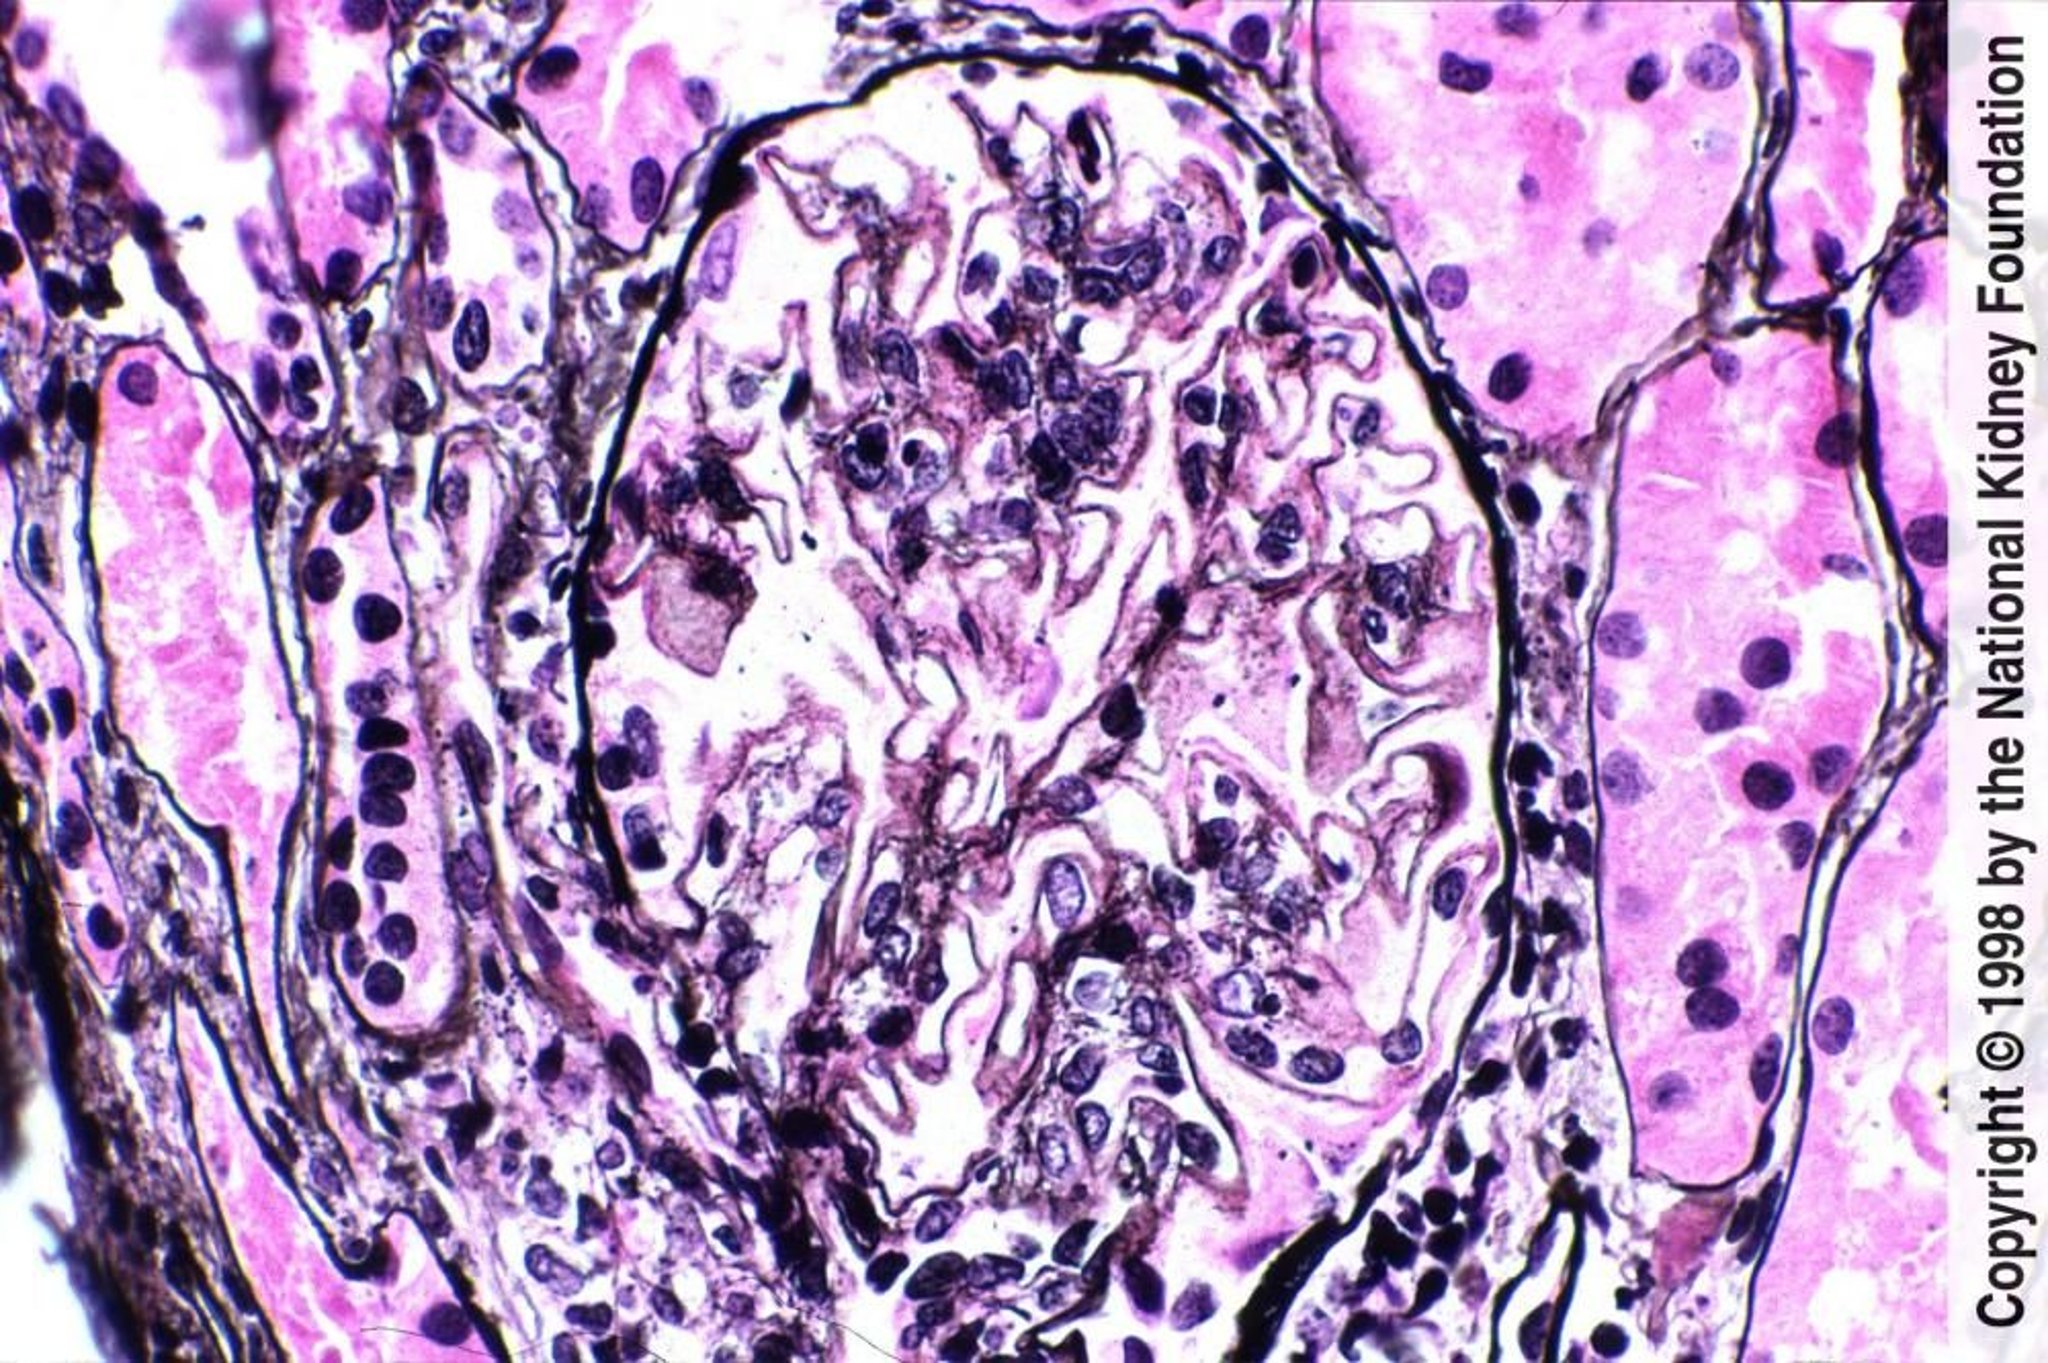

Néphrite lupique membraneuse (classe V)

Des trous diffus, de petites pointes et une légère expansion mésangiale avec de petites zones de coloration rose indiquent des dépôts de complexes immuns mésangiaux (coloration de Jones à l'argent, ×400).

Image fournie par Agnes Fogo, MD, and the American Journal of Kidney Diseases' Atlas of Renal Pathology (voir www.ajkd.org).